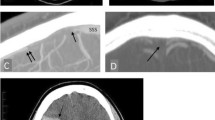

Headache is common in patients with leptomeningeal metastases. The incidence of headaches is estimated at 32% of patients at initial diagnosis and up to 75% throughout their disease course [11, 12]. The International Headache Society’s third edition of the International Classification of Headache Disorders (ICHD-3) defines “headache attributed to carcinomatosis meningitis” as requiring two of the three criteria in a patient with known leptomeningeal metastases: Headache has developed in temporal relationship to leptomeningeal metastases, headache has either significantly improved in the setting of improving leptomeningeal metastases or significantly worsened in the setting of progressive leptomeningeal metastases, and headache is associated with cranial nerve palsies and/or encephalopathy [13]. While this definition provides a useful framework, patients with leptomeningeal metastases can have several, sometimes overlapping, headache subtypes with distinct differences in pathophysiology (Fig. 1), presentation, and clinical management.

Pathophysiologic representation of five headache subtypes in patients with leptomeningeal metastases. In the setting of leptomeningeal metastases, cancer cells can be found free-floating in the CSF or adherent to the leptomeninges, transitioning between the adherent and floating states. a In disease-related meningeal irritation, sensory nerves embedded in the dura mater are theorized to experience innate-mediated activation. Myeloid cells (e.g., macrophage) and lymphoid cells (e.g., T cells) outnumber cancer cells, and higher levels of inflammatory cytokines (IL-6, IL-8, IL-1β) are observed. b Post-dural puncture headaches result from persistent CSF leakage incident to the dural hole and intracranial hypotension. On contrast-enhanced MRI brain, pachymeningeal thickening and enhancement are observed; a proposed explanation is compensatory dural vein engorgement. c Elevated intracranial pressure arises as cancer cells fill arachnoid granulations, disrupting the normal drainage of CSF from the subarachnoid space into dural venous sinuses. Brain imaging reveals communicating hydrocephalus or “ballooning” of the ventricles. d Intrathecal chemotherapy delivered via Ommaya reservoir causes a chemical arachnoiditis in the subarachnoid space, marked by increased leukocytes (T cells and macrophages), granulocytes (neutrophils), and inflammatory cytokines. e Ionizing radiation activates resident microglia, releasing pro-inflammatory cytokines (IL-6, IL-8, IL-1β, TNFα), chemokines (CCL2, CXCL2), and reactive oxygen and nitrogen species into the CSF. With increased blood-brain and blood-CSF barrier permeability, additional T lymphocytes and macrophages infiltrate the subarachnoid space and add to the inflammatory milieu

Clinical history is often sufficient to diagnosis PDPH, as the postural headache and temporal relationship with lumbar puncture is pathognomonic. Unless alternative etiologies are being considered due atypical features, confirmatory imaging is generally not necessary. The most common radiographic finding on contrast-enhanced MRI brain is pachymeningeal thickening and enhancement, which is distinct from disease-related leptomeningeal enhancement and is thought to reflect compensatory engorgement of the dural veins following reduction in CSF volume [57]. Pituitary enlargement, subdural effusions or hematomas, rounding of the dural venous sinuses, brain sagging, and tonsillar herniation are other less common features of intracranial hypotension [58].